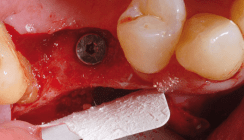

Der Behandlungsplan sah eine Extraktion des nicht zu erhaltenden Zahnes 27 gefolgt von einer beidseitigen Sinusbodenaugmentation entsprechend Tatum18 mit simultaner lateraler Augmentation sowie der Insertion von je vier Implantaten in den Bereichen 14–17 sowie 24–27 vor. Die Operation wurde unter Lokalanästhesie durchgeführt. Ein Mukoperiostlappen wurde nach Anlegen horizontaler, krestaler und sulkulärer Inzisionen abpräpariert. Der Lappen wurde mesial und distal durch vertikale Inzisionen entlastet. Für einen spannungsfreien Wundverschluss wurden Periostschlitzungen durchgeführt. Die Empfängerstelle wurde von Granulationsgewebe gesäubert. Es erfolgte auf beiden Seiten die Präparation eines rechteckigen Fensters in der lateralen Wand in Regio 15–16 bzw. 25–26, und die Schneider’sche Membran wurde vorsichtig angehoben (Abb. 2). Es wurden je vier Bone Level-Implantate (BIOMET 3i, L 11,5 bis 13 mm, Ø 4 und 5 mm) in Regio 14–17 und 24–27 inseriert. Die Augmentation der Sinuskavität in Regio 15–17 sowie 25–27 erfolgte mit zuvor in Defektblut rehydratisiertem deproteiniertem bovinem Knochen (Abb. 3). Die Bereiche 15–16 und 25–26 wurden leicht lateral überkonturiert (ca. 1–2 mm), um eine breitere bukkale Knochenstruktur für die inserierten Implantate zu schaffen. Das Knochenersatzmaterial wurde beidseits je mit einer OSSIX® Plus Membran 25 x 30 mm abgedeckt (Abb. 4). Aufgrund der guten Anliegeeigenschaften der Membran wurde auf eine zusätzliche Fixierung verzichtet. Der spannungsfreie Wundverschluss wurde durch Einzelknopfnähte erreicht.

Die Situation bei Wiedereröffnung zeigte einen vollständig konsolidierten Kieferkamm (Abb. 5). In Regio 14–15 waren noch deutlich Membranreste erkennbar (Abb. 6), die bereits deutliche Zeichen einer Integration in den Kieferknochen aufwiesen. Abbildung 7 zeigt einen typischen histologischen Befund sechs bis acht Monate nach einer Augmentation mit deproteinisiertem bovinem Knochenersatzmaterial und Membran (H&E-Färbung, mit freundlicher Genehmigung von Dr. Y. Zubery, Ramat HaSharon, Israel). Die Knochenpartikel sind eingebettet in ein Gemisch aus Bindegewebe und neu gebildeten Knochen. Direkt unter der Membran ist eine neu gebildete vitale Knochenschicht erkennbar. Der Membrankörper ist noch deutlich zu erkennen und zeigt Zeichen einer knöchernen Integration. Diese für eine Kollagenbarriere einmalige Beobachtung der Membranossifikation wurde bereits mehrfach in der Literatur beschrieben (Zubery 2007, 2008). Die Potenz der Knochenregeneration, die aufgrund der langen Barrierefunktion der Membran erzielt werden kann, lässt sich durch die Oberflächen textur des neu gebildeten Kieferkammknochens in Regio 15–17 erahnen, die derjenigen der Membran entspricht (Abb. 8). Abbildung 9 zeigt die radiologische Situation nach Installation der Gingivaformer mit einem ausreichend konsolidierten Kieferkamm, beide Sinusregionen zeigen ein ausreichend vorhandenes Knochenvolumen. Die finale Versorgung in Form von bedingt abnehmbaren verblockten VMK-Kronen erfolgte abschließend beim überweisenden Zahnarzt.